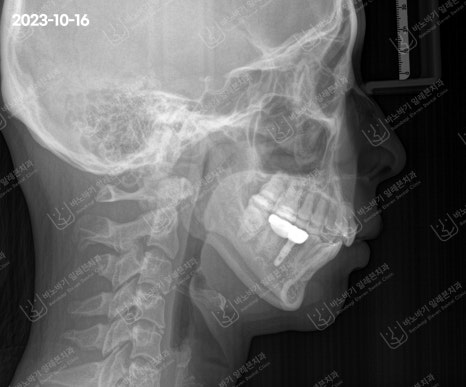

좀 더 구체적으로 살펴보고자 두경부 엑스레이를 촬영한 다음 골격 부조화를 검토하였습니다.

방사선 사진으로 보았을 때에 위턱과 아래턱 간 상하 균형이 적절한 수준으로 관찰됐습니다.

턱뼈의 크기도 이상이 없으며, 무턱 양상도 잘 안 보였습니다. 다만 앞니가 약간 깊게 물린 과개교합으로 확인되었습니다.